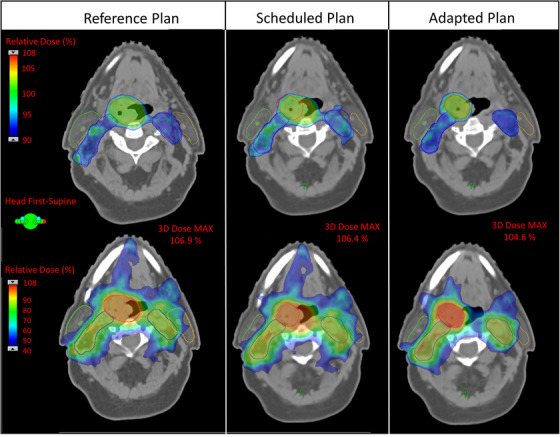

Figure 4 shows the dose color wash of the SEQ base reference, scheduled and adapted plans for a representative patient. This example illustrates the benefits of online plan adaptation. Due to response and subsequent target shrinkage, the dose in the scheduled plan was no longer conformal to or adequately covering targets as in the original reference plan. This results in a suboptimal plan with unnecessary high dose spill into adjacent mucosa as well as medium dose (i.e., 40% of the PTVHigh prescription dose, equivalent to 26 Gy) to nearby parotid glands that could potentially result in toxicity (e.g., xerostomia). By comparison, the adapted plan, reoptimized to the anatomy of the day with the clinical goals used to generate the reference plan, successfully rectifies these issues by maintaining desired target conformality, improved OAR avoidance, and improves homogeneity (Dmax < 105%) to even be superior to that of the reference plan.

FIGURE 4.

Dose color wash of the reference, scheduled and adapted Ethos plans for a representative SEQ base plan. The top and bottom rows show different slices with different dose colorwash ranges highlighting target coverage and OAR doses (e.g., parotid goal Dmean < 26 Gy here would be the 40% dose), respectively. Contours shown are: PTVhigh (red), PTVlow (blue), right parotid (green), and left parotid (orange). Note, compared to the reference plan, the adapted contour for PTVhigh (red) in columns 2 and 3 has decreased in size, resulting in over/under‐coverage and undesirable hotspots in the scheduled plan. Additionally, the scheduled plan shows the 40% dose spilling further into the left parotid. By comparison, the adapted plan provides conformality to the changed targets as well as better sparing of OARs and reduced heterogeneity (Dmax < 105%).